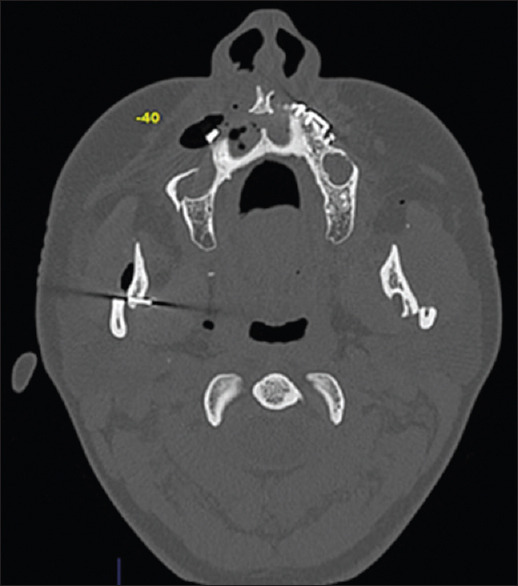

Diagnosis: Postoperative Computed Tomography (CT) images showed the broken blade embedded in the upper part of the right vertical ramus osteotomy.